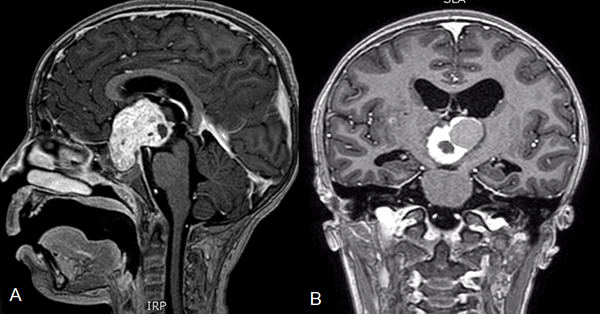

En los últimos años, se fue instalando una tendencia a un mayor interés a preservar la calidad de vida de los niños y adolescentes con craneofaringiomas.31 El mejor tratamiento para los craneofaringiomas pediátricos ya no sólo involucra la resección completa de la lesión sino la preservación de la función endocrinológica.32 Estos tumores son de crecimiento lento y requieren de un tratamiento crónico, siendo importante recordar que en la población pediátrica la mayoría de los tumores son quísticos y de gran tamaño (más del 60% del volumen tumoral).5,11,32 A partir de esta premisa es que han surgido procedimientos menos invasivos como el uso del sistema de Ommaya, que provee alivio de los síntomas y permite retrasar la cirugía agresiva hasta la completa maduración del eje hipotálamo-hipofisario(figura 2).29

Figura 2. Tomografía cerebral simple. A y B. Cortes coronal y sagital donde se observa un tumor predominantemente quístico con cápsula parcialmente calcificada. C y D. Cortes coronal y sagital postoperatorio con catéter colocado dentro del quiste tumoral para reducción progresiva del volumen del mismo. Se observa reservorio a nivel subgaleal.

El tratamiento de craneofaringiomas mediante Ommaya ha pasado por diferentes estadios. Las primeras series trataban el quiste con Bleomicina,11,34 luego se intentó el tratamiento con Inteferón donde el equipo del SickChildren de Toronto presentó resultados muy alentadores,34 y por último la aspiración del quiste sin introducir ninguna sustancia.5 Drenar el quiste mediante el sistema de Ommaya es útil ya que permite que se reduzca el tamaño de la lesión y disminuye el contacto con las estructuras circundantes. Se encuentra descripto que luego de múltiples drenajes del quiste, la exéresis de la lesión es menos dificultosa debido a que presenta menos adherencias al hipotálamo, a la carótida interna o al quiasma.33 Otra ventaja del drenaje del quiste es que permite desbloquear los forámenes de Monro y mejorar la hidrocefalia obstructiva.3 Si bien nuestra serie de pacientes con Ommaya es muy reducida para sacar conclusiones definitivas, no encontramos un empeoramiento de las evaluaciones clínicas de los pacientes en el postoperatorio. Sin embargo, sólo 2 pacientes se mantuvieron estables luego del tratamiento, en los otros 5 casos se requirió de un tratamiento alternativo. Esto no debería considerarse como un mal resultado ya que la finalidad de la colocación del Ommaya no es curar la enfermedad sino retrasar los síntomas para permitirles a los pacientes una correcta maduración del eje (figura 3).

Figura 3. A. Resonancia cerebro corte sagital donde se observa tumor a predominio quístico en la región selar supraselar compatible con craneofaringioma. B. Tomografía de cerebro corte sagital postoperatoria de colocación de catéter intraquístico. C. Radiografía cráneo perfil donde se observa catéter radiopaco con extremo en la región selar.